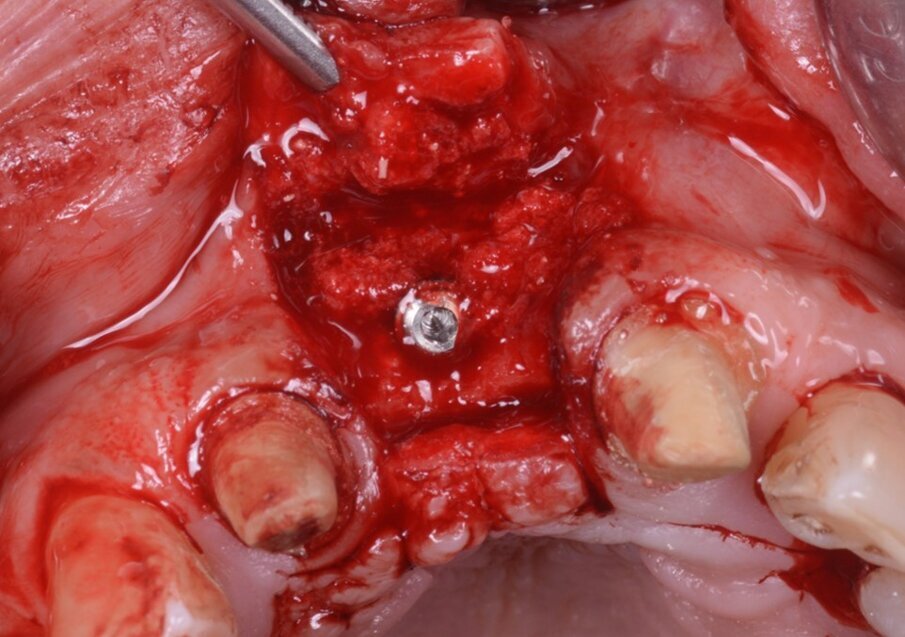

Nel frattempo, le dime chirurgiche erano preparate per la stampa (Fig. 12), stampate con potente stampante 3D stereolitografica (XFAB 3500PD, DWS Systems) e, dopo l’inserimento di boccola fresata in zirconia, pronte all’uso (Fig.13). La preparazione del sito chirurgico avveniva guidata, attraverso l’impiego di 3 mascherine chirurgiche identiche, caratterizzate però da boccole in zirconia con fori dal diametro differente (Figg. 14-17). Tali fori erano specifici per l’uso di ciascuna fresa, perciò non era necessario ricorrere all’uso di riduttori durante la preparazione; e dato che il template chirurgico conteneva già le informazioni relative alla profondità della preparazione, non occorreva impiegare alcuno stop in altezza. Inoltre, non era necessario impiegare frese lunghe, né kits per la chirurgia guidata: l’intervento veniva realizzato utilizzando un kit chirurgico standard, e a lembo aperto. Il posizionamento dell’impianto (Naturactis, Lyra ETK) (Fig. 18) avveniva infine manualmente, per non perdere la percezione della qualità ossea e della stabilità primaria nel sito rigenerato. L’osso recuperato dal sito di fresatura veniva riutilizzato per ulteriore filling vestibolare (Fig. 19).

Fig. 15_Sollevamento di lembo mucoperiosteo (spessore totale): si evidenzia la rigenerazione ottenuta con il blocco onlay di idrossiapatite che è fermamente adeso all’osso nativo. L’integrazione del blocco è evidente clinicamente.

Fig. 19_L’impianto è stato inserito, l’osso raccolto durante la preparazione del sito recuperato ed utilizzato per riempire vestibolarmente.